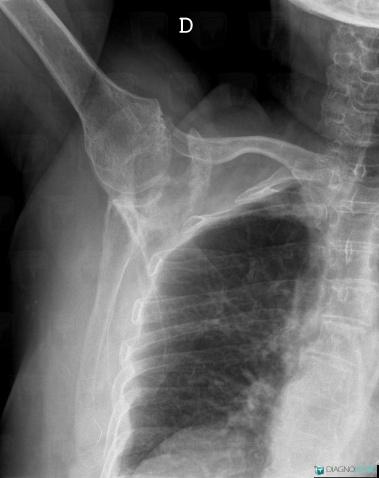

Metastasis, Scapula, X rays

Here is the specific information in the key image above:

- Diagnosis Metastasis, Location(s) Scapula, with gamuts Solitary osteosclerotic bone lesion